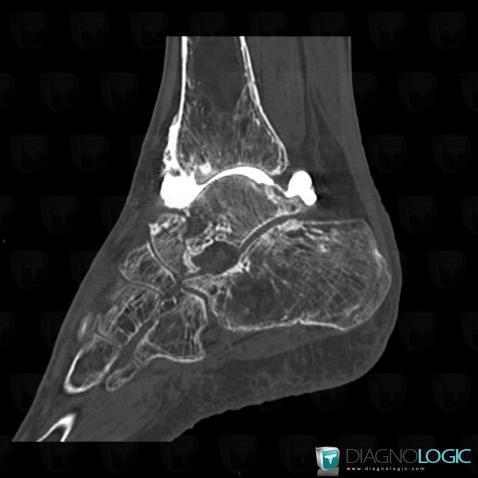

Bone infarct, Tibia - Distal part, CT

Here is the specific information in the key image above:

- Diagnosis Bone infarct, Location(s) Tibia - Distal part, with gamuts Mulltiple osteolysis, Multiple osteosclerotic bone lesions